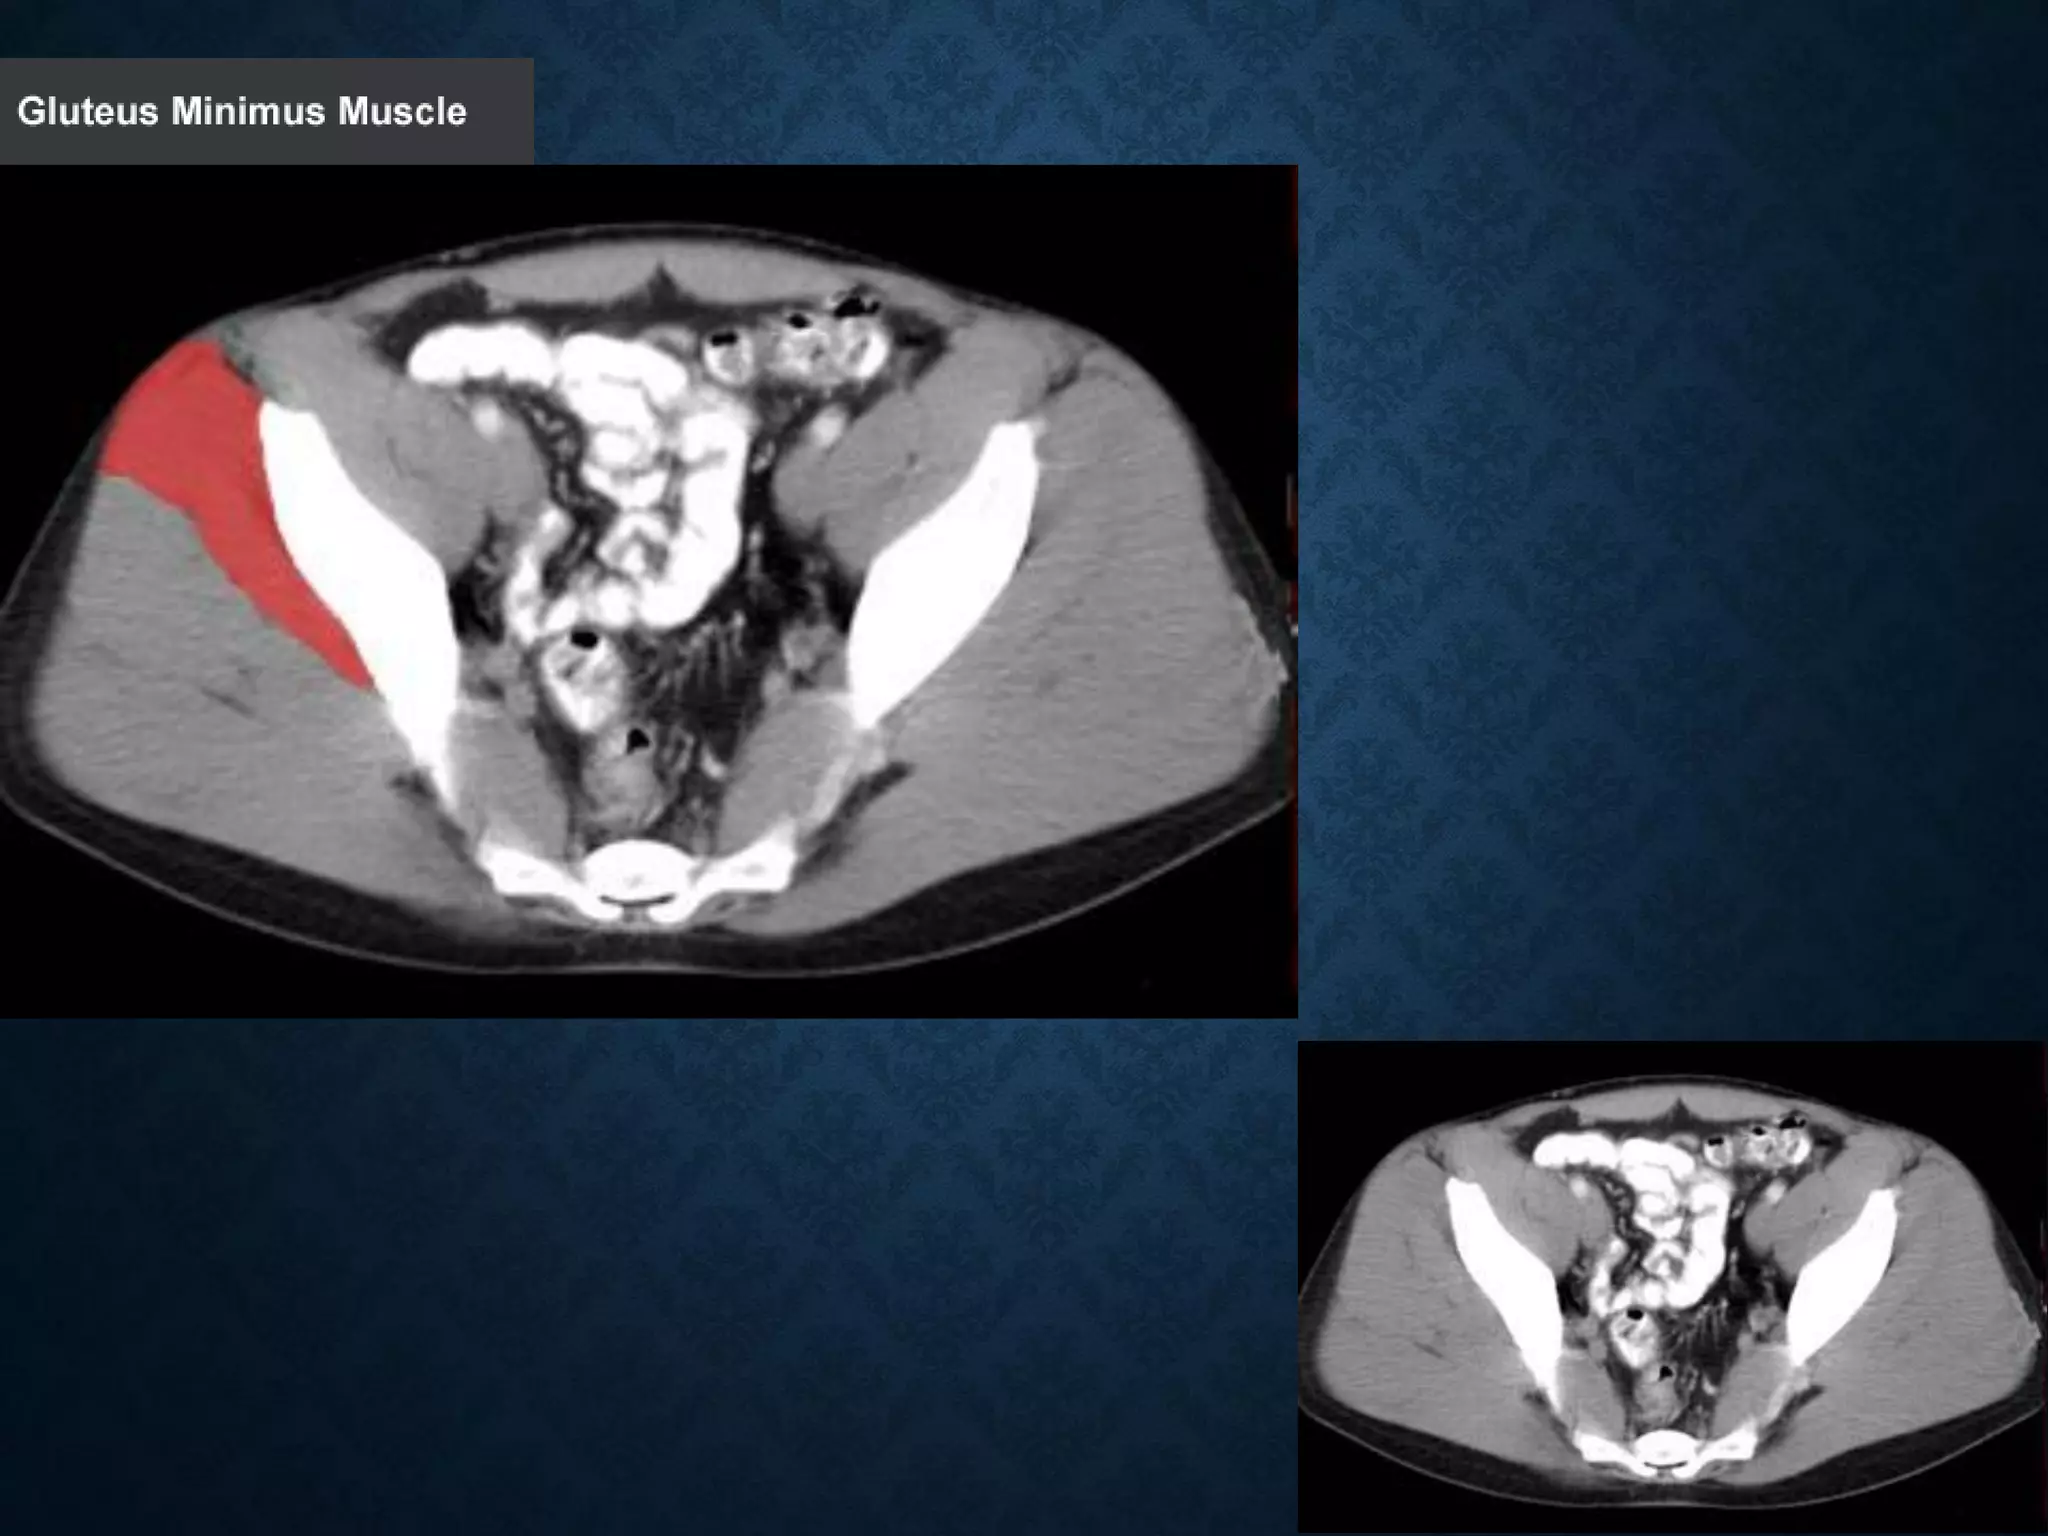

Identify the following structures in the body CT to the right. To view the location of the structure in the image click on

the label at the left and the structure will be indicated in the image. Abdominal CT scans typically begin just above

the diaphragm, so the first slice you see is of the lower chest.

Normal Anatomy- Section 12

Normal Anatomy- Section 13